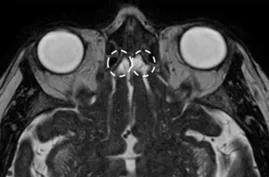

A Steady-state free precession (SSFP) axial image showing the olfactory nerves (arrows).

A Steady-state free precession (SSFP) axial image showing the abducens nerves (circles).